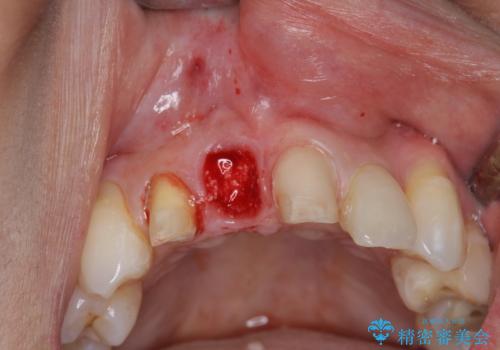

- 前医に前歯の吸収による抜歯の必要性を伝えられ、前歯の審美的な改善・治療を求めて来院されました。

CT撮影を行った結果、右上前歯は吸収が進み抜歯が必要な状態です、

抜歯をせず放置すると、より吸収が進み臨在する歯にも悪影響を及ぼしてしまう可能性が考えられます。